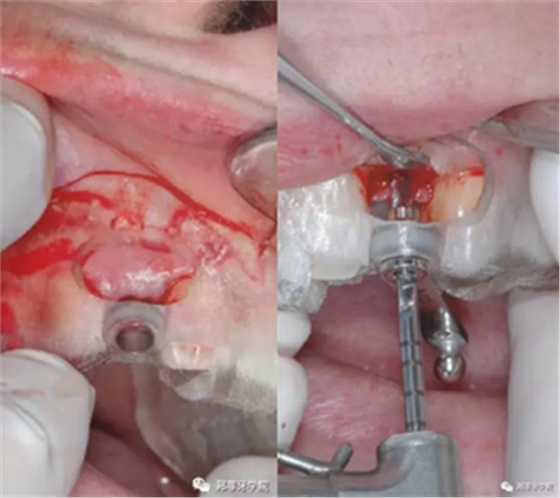

本病例中,缺隙足夠在保持天然牙與植體之間最小距離1.5mm的情況下兩側(cè)各植入1枚3.5mm Nobel Replace Tapered Groovy植體。手術(shù)導(dǎo)板設(shè)計(jì)頰側(cè)開窗,方便操作及固位。采用嵴頂切口,翻粘骨膜瓣(圖5 & 6)。

圖5 & 6:手術(shù)導(dǎo)板頰側(cè)開窗設(shè)計(jì)

采用手術(shù)導(dǎo)板進(jìn)行備洞及植入,植入扭矩35Ncm。植體適當(dāng)偏腭側(cè)植入,避免鄰近結(jié)構(gòu)破壞及前庭處骨外壁穿孔。植體肩臺(tái)位于鄰牙釉牙本質(zhì)界根尖方2mm(圖7&8)。

圖7 & 8:導(dǎo)板下備洞及植入